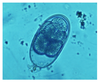

Swine and humans = both are infective

Mouse abdominal fluid

Toxoplasma gondii

Motile tachyzoites

DH: cat

Mouse brain

Toxoplasma gondii

Cyst with bradyzoites

Thin walled sporulated sporocyst in fecal float

All mammals

DMSO carbol fuschin stain

Cryptosporidium parvum

Pink stained oocysts

Small oocysts

4-8 naked sporozoites in fresh feces = NO sporocyst

Does not need to sporulated to be infective

All mammals

Cryptosporidium parvum

Oocysts on villi of small intestine